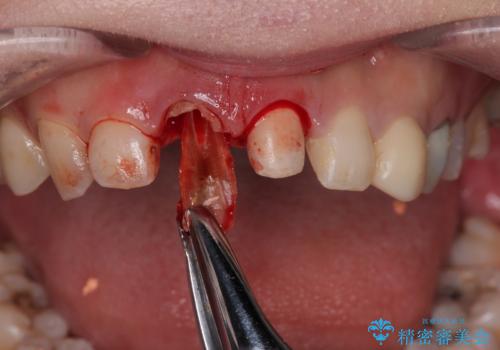

▶右上中切歯

抜歯後、即時インプラント埋入

精密検査の結果、右上中切歯には**フェルール(歯の周囲の健全な歯質)**がほぼ存在せず、このままの状態での保存は困難と判断しました。